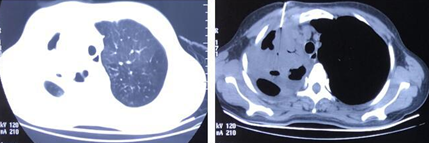

患者入院前2周感冒受凉后出现胸背部钝痛伴轻度呼吸困难,未在意,自服“感冒药”无好转。10天前呼吸困难进行性加重,胸部CT提示右肺上叶斑片状渗出影伴实变,内有少许空洞,中叶部分实变(图1)。当地医院给予头孢噻肟抗感染治疗3天,呼吸困难持续加重,后出现Ⅱ型呼吸衰竭伴意识障碍、发热。外院给予气管插管联合呼吸机辅助通气,同时将抗感染药物调整为亚胺培南西司他丁+利奈唑胺治疗4天,患者病情改善不明显,遂转入我科。自发病来患者精神、饮食、睡眠差,二便正常,体重减轻约5 kg。

图片

图1  患者胸部CT